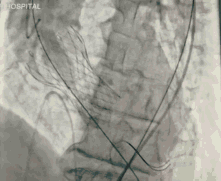

葛均波院士、周达新教授结构团队对这位生物瓣衰败的老年男性患者行瓣中瓣植入术,术中选择了23mm VenusA-Valve(杭州启明),植入过程顺利,术后冠脉无堵塞,未出现瓣周漏,术后跨瓣压差接近于0,赢得了参会专家的激烈掌声。

图4 TAVR球囊前扩张

图5 TAVR瓣膜释放后